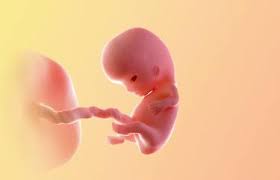

Check out the illustration below to help you imagine how things are taking shape within the uterus when you are nine weeks pregnant. Jun 24, 2021 · how big is my baby at 9 weeks? Your baby is 2 months old! Learn more about symptoms and what to expect at 9 weeks with babycenter. Until the end of the period, it increases by 500 times compared to its original size. Your baby is about the size of a grape your baby now weighs a fraction of an ounce and is almost 1 inch long. Jan 22, 2020 · at 9 weeks of pregnancy the uterus is actively growing. Surprised by the size of baby at 9 weeks?

Until the end of the period, it increases by 500 times compared to its original size. First shots, "mental leaps" and the sense that you've come a long way from labour and delivery. What you can do at 9 weeks now that you know what your 9 weeks pregnant belly and the baby will look like, let's discuss what you can do at this stage of your pregnancy. Check out the illustration below to help you imagine how things are taking shape within the uterus when you are nine weeks pregnant. Your baby is about the size of a grape your baby now weighs a fraction of an ounce and is almost 1 inch long. Nov 11, 2020 · 9 weeks: Jan 22, 2020 · at 9 weeks of pregnancy the uterus is actively growing. Today's parent october 1, 2018. At 9 weeks pregnant, your little one is now about 1 inch long, the size of a medium green olive — but no martinis, please. Your little one may now measure 0.6 to 0.7 inch long and weigh about 0.12 ounce. At this term, it's similar in size to a grapefruit. How big was your belly at 9 weeks pregnant? Baby is the size of a cherry at 9 weeks pregnant.